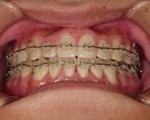

CASE5

小学1年の頃から前歯の噛み合せが逆でした。

同級生が通っていたので来ました。

(11歳/男性)↓

概要・担当医コメント:反対咬合・前歯部咀嚼障害↑

/マルチブラケット装置/非抜歯/動的治療期間24ヶ月(25回)/費用概算:60万円

治療前は虫歯のコントロールが難しい状態でしたが,矯正治療を開始してからは歯磨きを丁寧にしてくれるようになり,甘味摂取習慣の改善も行って頂いた効果があり,その後の虫歯の発生は無く現在に至っています.